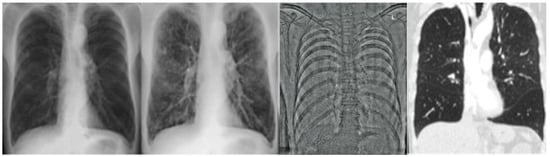

2.2.1. CR and DE Images

2.2.2. CT Images